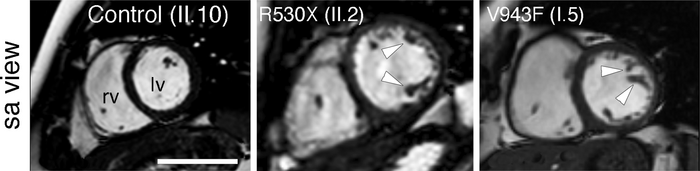

The team verified the data in mouse models. “When we simultaneously introduced the set of mutations identified in one of the two LVNC families, the mice developed heart chamber defects, leading to an LVNC-like disease and affecting heart function. In contrast, the set of mutations from the other family caused valve defects, showing that the additional variants function as modifiers of the effect of the Mindbomb1 mutation,” explained Marcos Siguero Álvarez.

A key feature of these experiments was that only one allelic copy of each gene mutant was inserted into the mice. In other words, as seen in patients, the mutant variants generated the phenotype through a dominant effect.